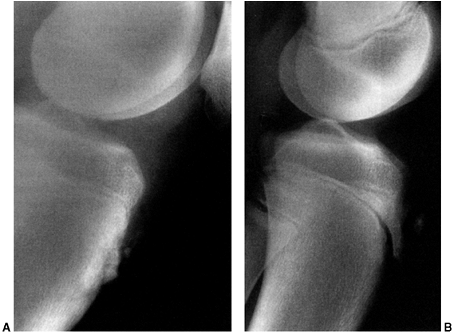

accompanies an acute patellar dislocation. Plain radiographs,

specifically anteroposterior, lateral, and Merchant view (also known as

skyline views) should be carefully

evaluated for patellar reduction, lateral tilt, and osteochondral

fracture. The Merchant view is an axial view of the patellofemoral

joint with the knee flexed to a consistent 35 to 45 degrees (41) (Fig. 32.1).